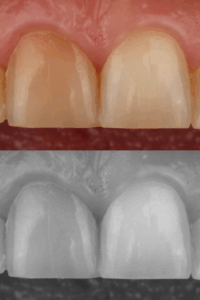

• Kontroliuoti spalvą, vertę ir maskavimą kompozito sluoksniavime

• Spalvos kontrolė, opakerių ir dentino masių naudojimo logika.

• Opakerių taikymas ir maskavimo strategijos.

• Dentino ir emalio sluoksniavimo seka tamsiam fonui.